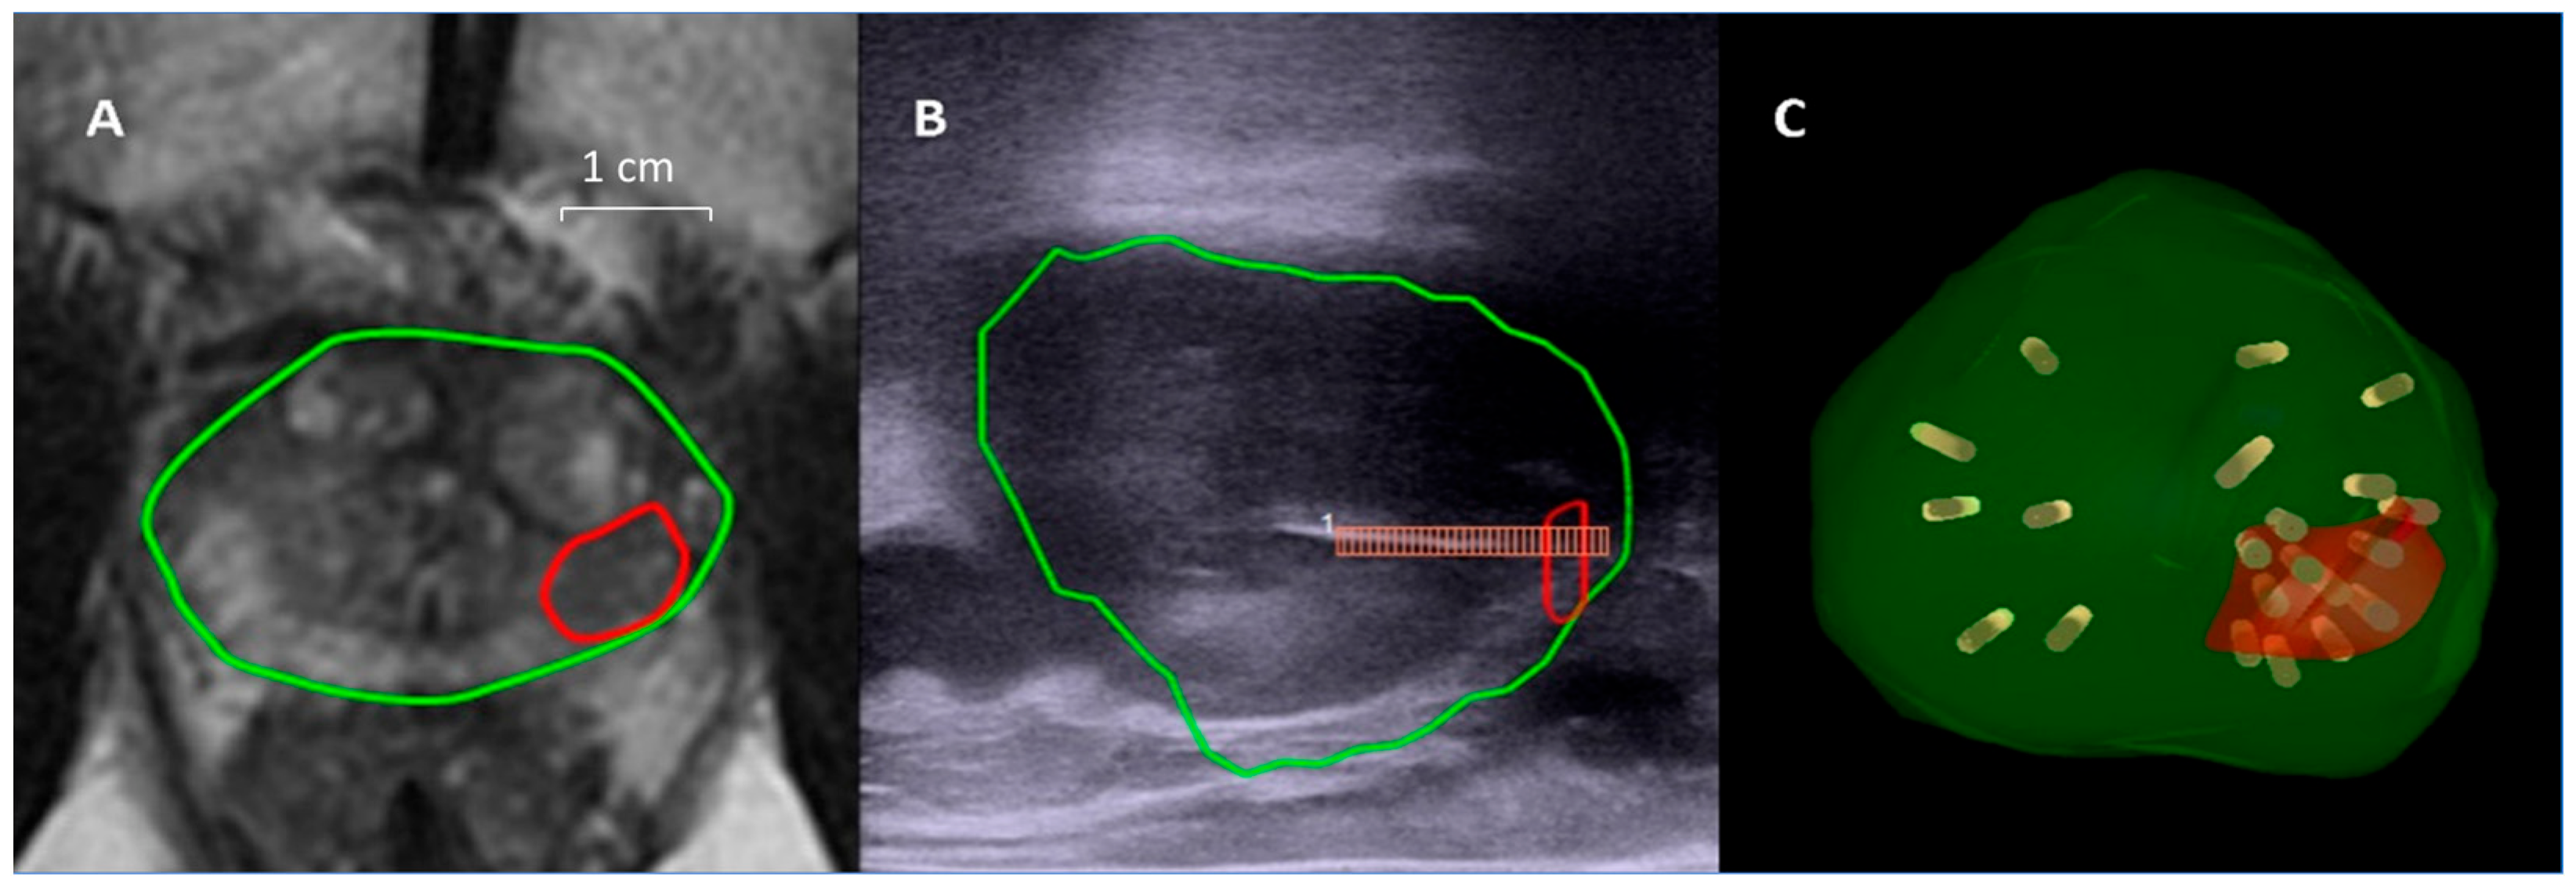

Under general anesthesia with endotracheal intubation and prophylactic antibiotics with levofloxacin, the patients were placed in the lithotomy position. A transrectal probe (BK 8848, BK Medical, Peabody, MA, USA) was first used to obtain a US scan of the prostate. The segmented mpMRI images were then overlaid on the real-time US images in the fusion platform using a rigid or elastic registration. With regards to the image tracking mechanism, the BioJet system used mechanical arms with built-in encoders, and the bkFusion system used electromagnetic navigation. After confirming the alignment of prostate contours on mpMRI and US in both the transverse view and sagittal view, MRI/US fusion targeted biopsy (TB) was done with at least two cores in each target lesion. Subsequently, SB was performed following the Ginsburg protocol, in which biopsy cores were taken from 12 sectors of the prostate [27]. The biopsy samples were obtained using an 18 G biopsy gun with a specimen size of 22 mm (Bard Magnum; Bard Medical, Covington, KY, USA). The SB samples were put in 12 bottles according to each sector, and the TB samples were put in additional bottles according to the number of target lesions. All biopsies were performed transperineally by a single urologist (P.F.H.) with 7 years of experience in transrectal cognitive prostate biopsy. Initially a brachytherapy grid was fixed on the stepper on the mechanical arm in the BioJet system to guide the biopsy routes, and since 2021 a free-hand biopsy technique without the brachytherapy grid has been used exclusively [28,29]. Only a free-hand biopsy technique was allowed in the bkFusion system. All of the biopsy trajectories were recorded on the MRI/US fusion platform, and a video of the biopsy procedure was recorded for each patient (Figure 1).

Figure 1. Example of MRI/US fusion prostate biopsy. A target lesion of 10 mm (red circle) was noted in the left peripheral zone near the apex of the prostate (green circle), and the PI-RADS score was 4 (A). The sagittal view of real-time US showed the biopsy needle puncturing through the target (B). All of the biopsy trajectories were recorded in a 3D model (C). Gleason 3 + 4 adenocarcinoma involving 80% of the TB cores was found on histopathological analysis. The patient received radical prostatectomy, and Gleason 3 + 4 adenocarcinoma on the left lobe was confirmed, involving 1.6% of the prostate volume.